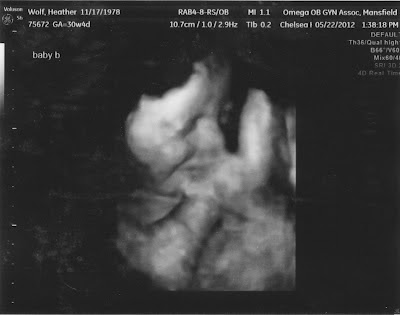

| here is our baby boy - he's facing the right and if you look closely he's got a cute smile =) |